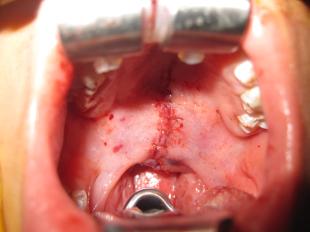

Cleft Palate Surgery - Before and After

Kung Plastic Surgery offers cleft palate surgery for residents of Chevy Chase, MD and Washington, DC. Cleft palate surgery closes the palate in order to restore the normal functions of the mouth with regard to eating and drinking, as well as enhance the development of the patients’ normal speech. Please enjoy these before and after pictures of cleft palate surgery.